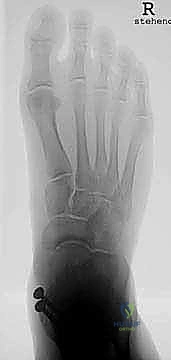

* التصوير الشعاعي المتقدم: صور أشعة سينية (X-rays) في وضعية الوقوف (تحميل الوزن) لتقييم المحور الميكانيكي للساق والقدم.

* الأشعة المقطعية (CT Scan): للحصول على رؤية ثلاثية الأبعاد للعظام، تقييم حجم التكيسات العظمية (إن وجدت)، والتخطيط الدقيق لحجم المكونات المعدنية.

* تقييم التوازن: التأكد من عدم وجود تشوهات في القدم (مثل القدم المسطحة الشديدة أو التقوس) التي قد تؤثر على عمر المفصل الصناعي. إذا وجدت هذه التشوهات، قد يقرر الدكتور هطيف إصلاحها جراحياً في نفس الوقت لضمان بيئة ميكانيكية مثالية للمفصل الجديد.